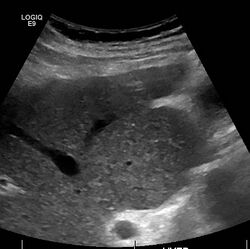

Caudate lobe hypertrophy on ultrasound due to cirrhosis

Imaging

Ultrasound is routinely used in the evaluation of cirrhosis.[36] It may show a small and shrunken liver in advanced disease. On ultrasound, there is increased echogenicity with irregular appearing areas.[54] Other suggestive findings are an enlarged caudate lobe, widening of the fissures and enlargement of the spleen.[55] An enlarged spleen, which normally measures less than 11–12 cm in adults, may suggest underlying portal hypertension.[56] Ultrasound may also screen for hepatocellular carcinoma and portal hypertension.[36] This is done by assessing flow in the hepatic vein.[57] An increased portal vein pulsatility may be seen. However, this may be a sign of elevated right atrial pressure.[58] Portal vein pulsatility are usually measured by a pulsatility indices (PI).[57] A number above a certain values indicates cirrhosis (see table below).